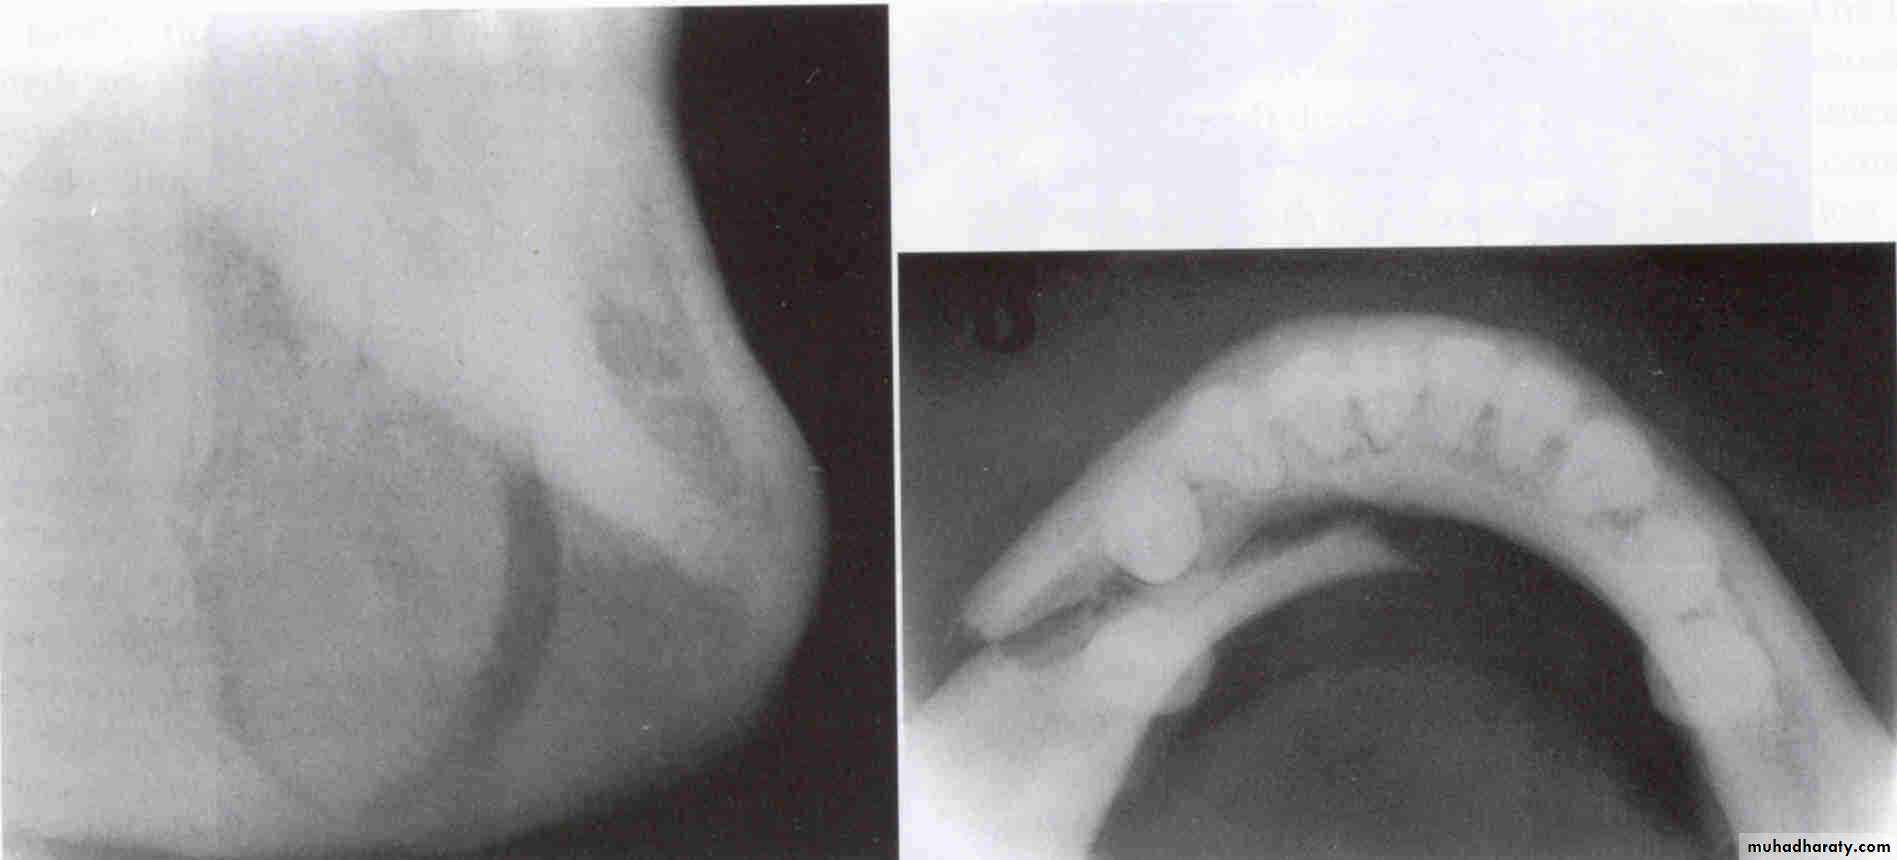

WATERS VIEW(Occipitomental )

LATERAL VIEWLateral oblique

Occlusal view